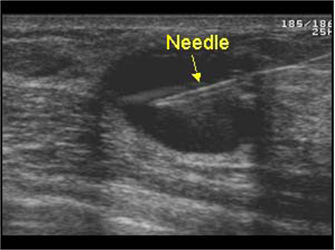

ε) Για να πραγματοποιήσουμε επεμβατική πράξη, όπου καθοδηγούμε τη βελόνα με τους υπερήχους για βιοψία συμπαγούς μορφώματος (εικόνα 4) ή εκκένωση κύστης (εικόνες 5,6) ή τοποθέτηση συρμάτινου οδηγού σε ογκίδιο για την ακριβή εξαίρεσή του χειρουργικά.

(Εικόνα 5)